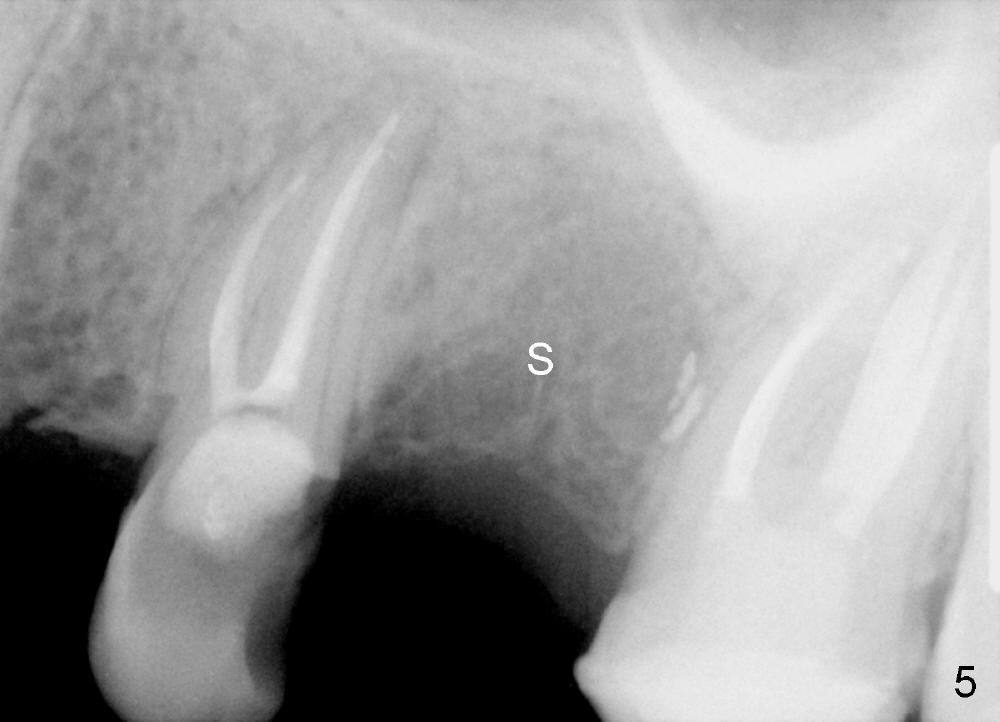

The socket looks empty two months post-extraction (Fig.4 S). Bone appears to re-grow in the socket 9 months after extraction (Fig.5 S), but the buccal plate is severely atrophic and concave (Fig.6 arrowheads). When an incision is made, the socket feels soft. Osteotomy is created by bone expansion (round tapered osteotomes (RT) 2,3,4 mm). Drilling is done once, using 3.5x17 mm tapered drill when the larger RTs meet resistance near the sinus floor. Tapered taps are used to continue to expand the osteotomy (4.5 (Fig.7), 5.0 and 6.0x20 at the depth of 17 mm). Finally 6.0x17 mm implant is placed with insertion torque more than 60 Ncm (Fig.8). The buccal plate is less concave with bone expansion and implantation (Fig.9 arrowheads). Without immediate implant, bone resorbs quick, which makes delayed implantation difficult.